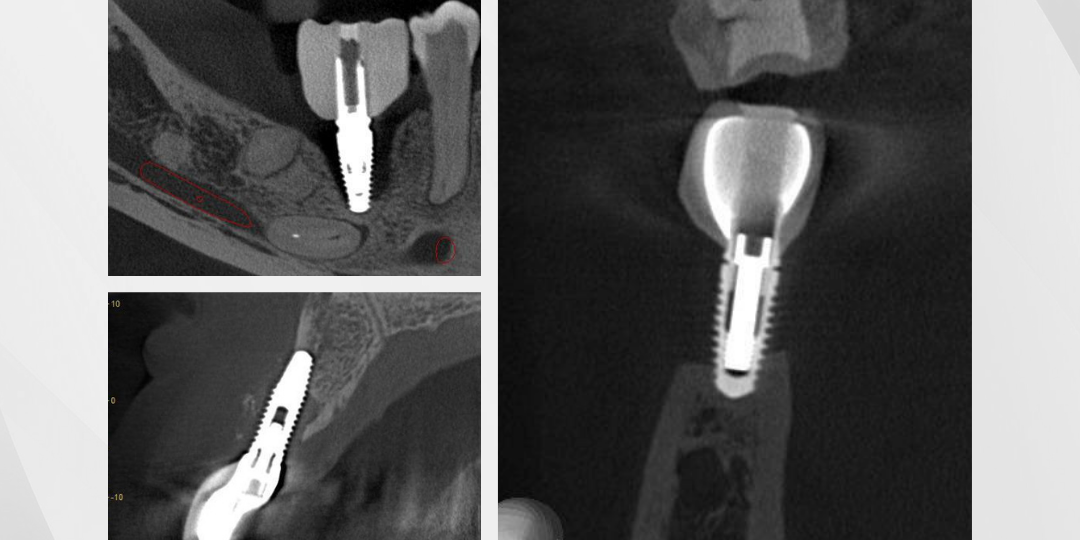

Nesta análise tridimensional de perda óssea, a tomografia a evidencia significativamente ao redor do implante, permitindo uma avaliação detalhada da progressão da reabsorção e seu impacto estrutural.

O que os cortes tomográficos revelam?

Comprometimento ósseo peri-implantar – A imagem mostra uma área de reabsorção óssea ao redor do implante, indicando um possível processo inflamatório ou falha na osseointegração. Em síntese, a extensão da perda pode impactar a estabilidade do implante e a longevidade da reabilitação.

Atingimento da cortical óssea – A análise tridimensional de perda óssea em diferentes planos permite observar o envolvimento da cortical vestibular e lingual, que pode estar afinada ou rompida. Isso, um fator determinante para a conduta clínica e necessidade de regeneração óssea.

Espaço biológico e adaptação da prótese – A tomografia também permite avaliar se o desenho protético está influenciando a resposta óssea. Desse modo, observando possíveis sobrecargas que podem estar acelerando o processo de reabsorção.

Proximidade com estruturas anatômicas – É possível visualizar a relação do implante com estruturas críticas, como o canal mandibular.

Portanto, a tomografia não apenas confirma a presença da perda óssea. Mas também, fornece dados essenciais para mensurar sua extensão, avaliar sua relação com o implante e definir a abordagem ideal para tratamento e controle do caso.